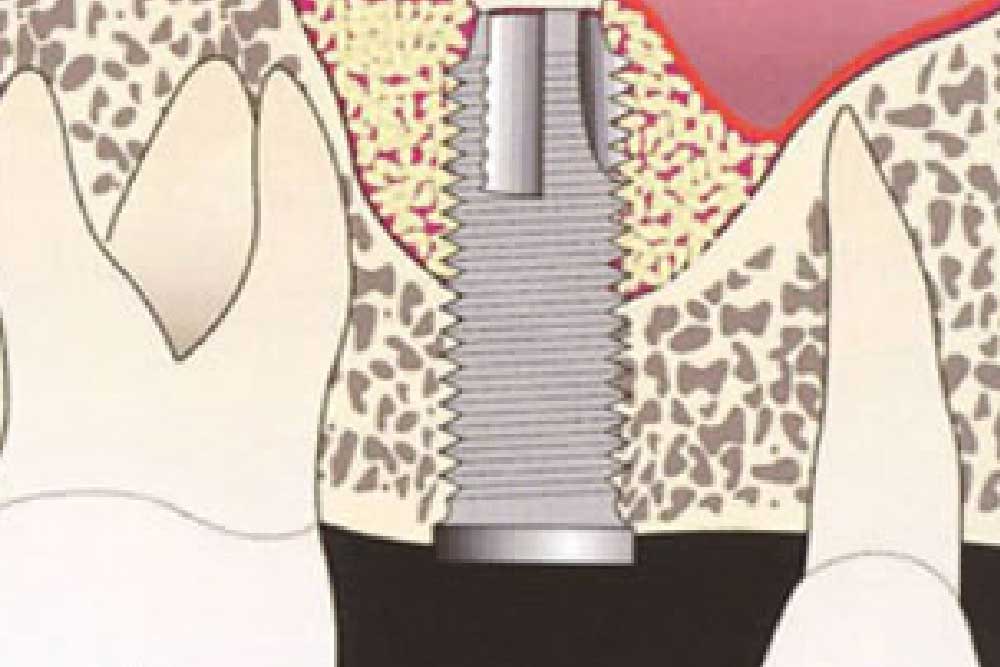

歯科治療におけるインプラントとは、歯を失った部分の顎骨に生体親和性の高いチタン製などの人工歯根を埋め込み、その上に人工の歯を取り付けて咬み合わせを回復するという治療法です。

歯科治療におけるインプラントとは、歯を失った部分の顎骨に生体親和性の高いチタン製などの人工歯根を埋め込み、その上に人工の歯を取り付けて咬み合わせを回復するという治療法です。

入れ歯やブリッジにはない歯根が存在するため、安定性が高く、より天然歯に近い感覚でお使いいただけます。外科処置についても、一般的な症例であれば通常の歯科治療と同じ位の時間で完了し、入院なども必要ありません。

ストローマンインプラントは、1974年に創業した歴史のあるインプラントメーカーで、今尚、研究に力を入れ、日々進歩しています。日本人の骨格に適したインプラントの形状をはじめ、骨との結合が早いこと、さらに長期維持の症例が多いことが特徴です。